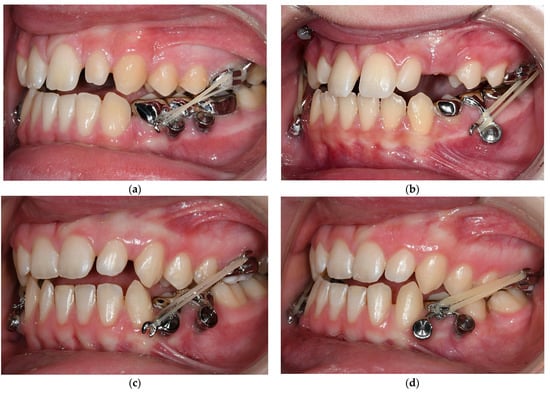

3.3. Treatment Progress